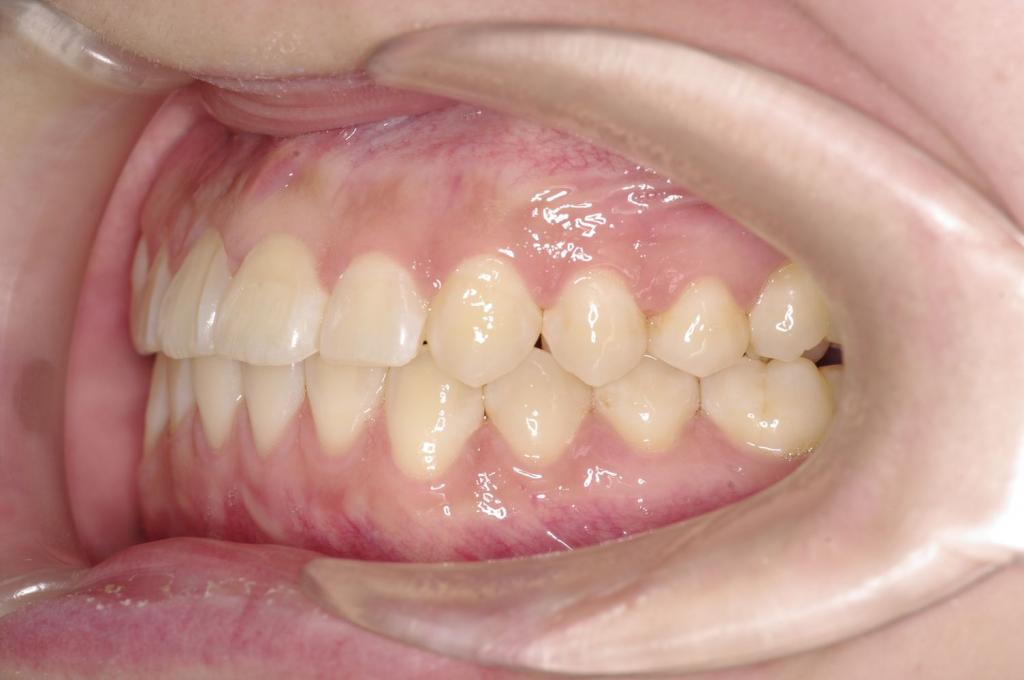

前歯、出っ歯・開咬の矯正治療

(治療期間、治療前後写真、治療方法、費用)WORKS